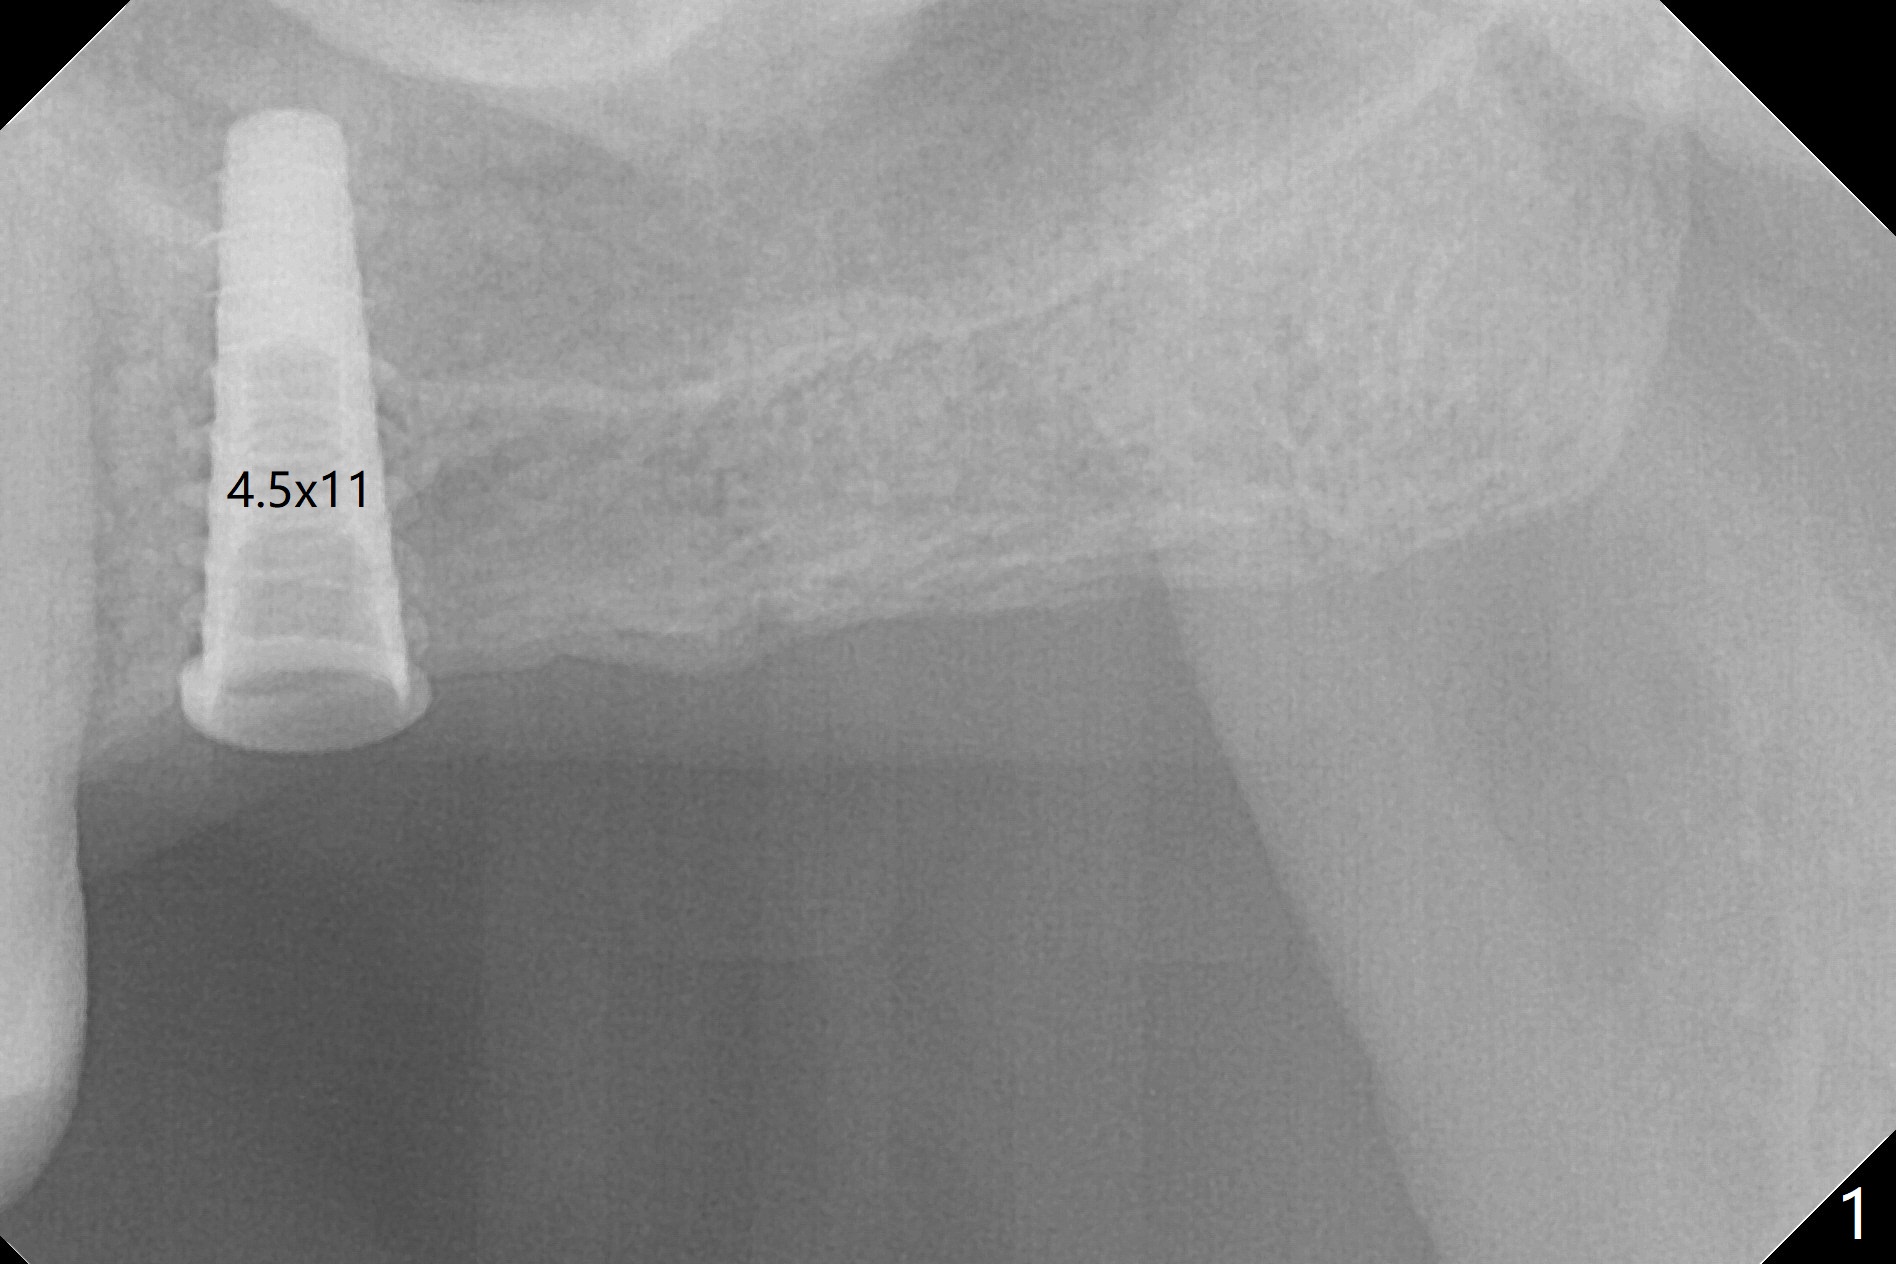

The long 4.8 mm Magic Drill (MD) is used as a tissue punch at the site of #14. After use of a curette to remove the tissue, the MD is used for osteotomy. In fact the osteotomy is mesial with an increase in the osteotomy depth. Magic Lifter, Magic Expander (3 mm) and Magic Drill (3.8 mm) are used to finish sinus lift. Following placement of PRF and Vanilla Graft, a 4.5x11 mm dummy implant is placed (Fig.1,2). The osteotomy seems to be mesial. After use of Lindamann bur distally and 2nd round of PRF membrane and Graft, a 5x9 mm implant is placed > 50 Ncm (Fig.3,4). The final implant appears to remain mesially radiographically. Retrospectively, 1.6 mm pilot drill should have been used with insertion of guide pin after tissue punch. Change in osteotomy position would have been much easier at the early stage. The patient returns for impression 3 months postop; There appears to be space mesial to the implant (Fig.5). The permanent crown will be cemented 2-3 months later. No screw loosens probably related to mesial placement of the implant.